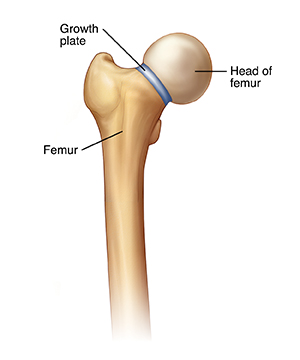

Your child has been diagnosed with a condition called slipped capital femoral epiphysis (SCFE). This means that the femoral head (the ball at the top of the thighbone) has slipped slightly off the thighbone. (It may help to picture a scoop of ice cream slipping off of a cone.) This problem can be very serious if not treated. Your child will likely be referred to an orthopedist, a healthcare provider specializing in treating bone and joint problems, for evaluation and treatment.

In rare cases, even with treatment, the hip joint can still have problems. This is more likely if the growth plate was injured by the slip. The growth plate is a soft part of a long bone that allows the bone to grow as the child grows. Disruption of the blood supply to the femoral head during the slip may also lead to problems. Problems are more likely with severe SCFE. Catching these problems early is one reason why it's vital to continue to follow up with the surgeon as your child grows.